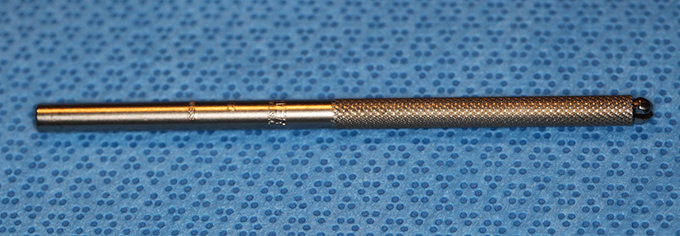

Knife Handle, Beaver 3K 4in)

Beaver

Typical Use(s): Holding blades; (Rarely used)